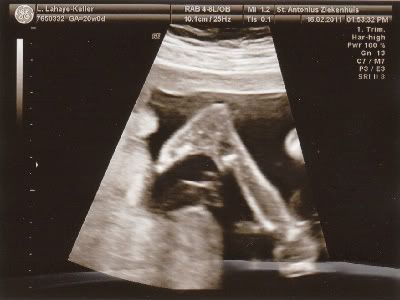

Lijkt me duidelijk wat het wordt hahahahaha.....!!!

Voor degene die niet zo goed in echo's zijn......

We gaan straks beschuit met blauwe muisjes smeren!